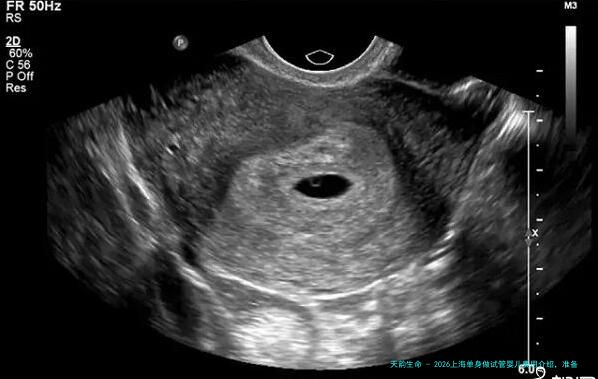

试管婴儿的基础治疗费用(不囊括药品费用)大概在10,000元到30,000元之间不等。这些费用蕴含了所有的医疗检查和诊断过程,如卵巢超声检查、血检等等。